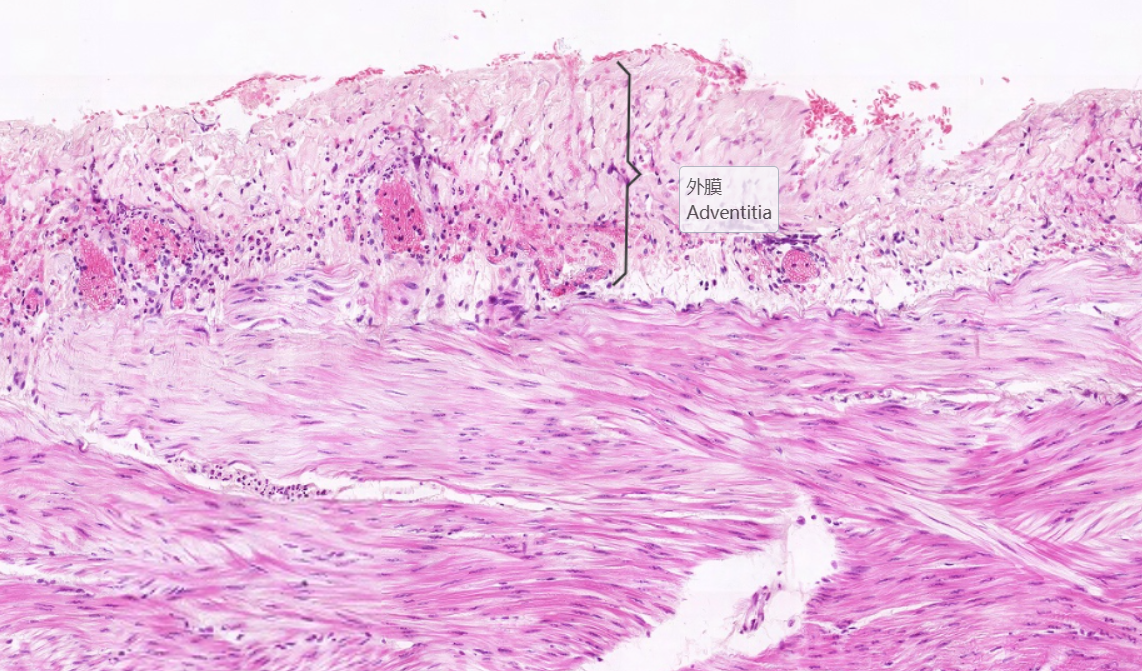

4.外膜